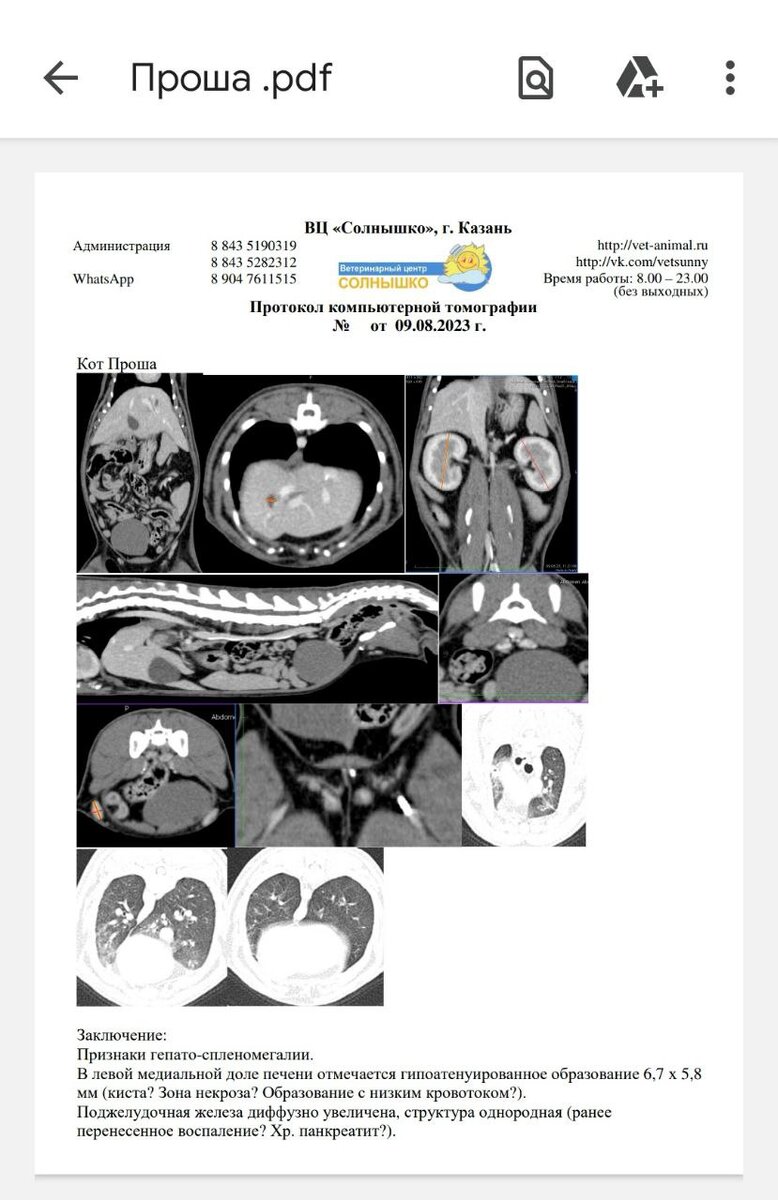

Пришло заключение КТ котика Проши. Нужно дообследование.

Вчера куратор котика Проши Юля с сыном возили его на КТ в г. Казань. Уже очень поздно к вечеру пришло заключение, где чётко не прописано наличие метастаз. Документ сразу переслали врачу- онкологу. В описании есть моменты, которые ему не совсем понравились и он назначил допобследование. Рентген грудной клетки и УЗИ брюшной. Пока картина, характерная для ВИК. Но нужно обязательно все перепроверить ещё. По результатам этих исследований будет принято решение на счёт того, нужна химиотерапия или нет.